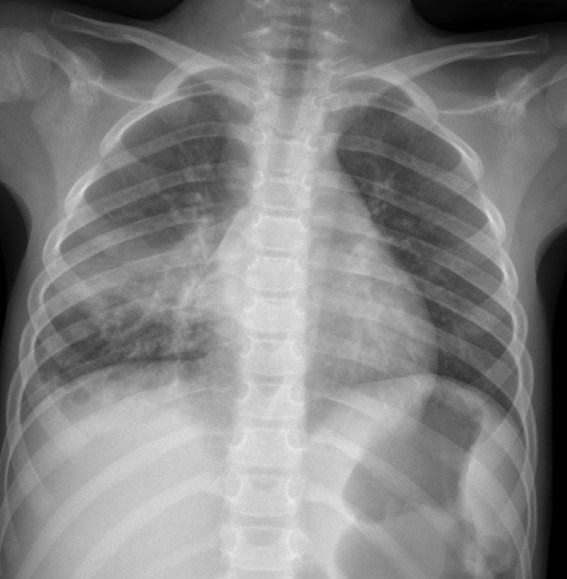

CASO: Operada de esofaguectomia y reconstrucción con coloplastia hace 3 meses. Sintomas de neumonía.

Hallazgos:

- De inicio llama la atención una densidad practicamente total del todo el hemitórax izquierdo, lo cual podría hacernos pensar que estamos ante una posible neumonía.

- Sin embargo el tórax está no está bien centrado, observar como la clavícula izquierda se encuentra casi en la mitad del pulmón, por tanto lo que vemos blanco es el mediastino ya que el tórax está rotado.

CENTRAJE:

El correcto centraje se determina comprobando que las extremidades internas de ambas clavículas equidistan de las apófisis espinosas vertebrales.

Mismo paciente, al cual esta vez se le ha tomado una radiografía en PA y en sedestación. Observar como las clavículas están equidistantes a las apófisis espinosas y como ha desaparecido el velamiento del pulmón izquierdo.

Por otra parte, paciente presenta una cardiomegalia y un discreto ensanchamiento del mediastino es probable relación con cambios postquirúrgicos.